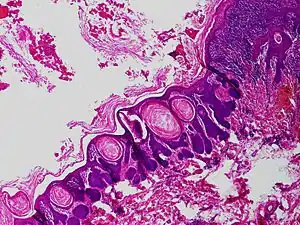

Trichofolliculoma

Trichofolliculoma is a cutaneous condition characterized by a benign, highly structured tumor of the pilosebaceous unit.[1][2] Trichofolliculoma is a rare tumor of the eyelid. It can be suspected by the “cotton bag sign”[3]